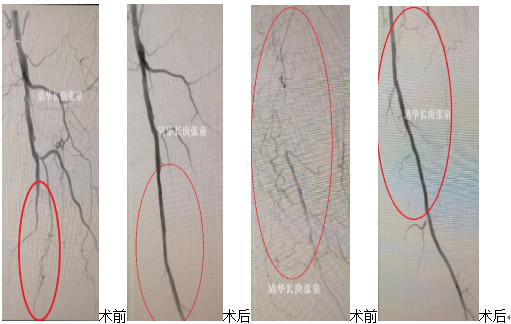

该治疗不仅可以直接清除斑块,恢复血流,而且是通过特别小的穿刺点实现的(图7),治疗后血管内不留下任何异物材料,最大限度地减少了术后血管内膜增生引起的再狭窄。腔内斑块切除术可以治疗腹股沟以下动脉病变,尤其适用于一些不宜植入支架的位置,如股总动脉、腘动脉及膝下血管等。

药涂球囊(Drug-coated balloon,DCB)是在扩张血管的球囊表面涂敷抑制内膜增生的紫杉醇、雷帕霉素等药物,在扩张病变的同时将药物释放在血管内膜,抑制内膜中膜增生,提高了中远期通畅率。多个著名临床研究结果,证实了药涂球囊的疗效显著。斑块旋切结合使用药涂球囊,最大限度的提高了通畅率,符合腹股沟以下动脉病变“少支架”甚至“无支架”治疗的理念(图8)。

后续(图9):王大爷下肢恢复了血流,腿也不疼了,行走轻松,愉快的出院回家了,我们陆续又为其他三十余例下肢动脉严重硬化闭塞的患者实施了同样的手术,取得了满意的疗效。